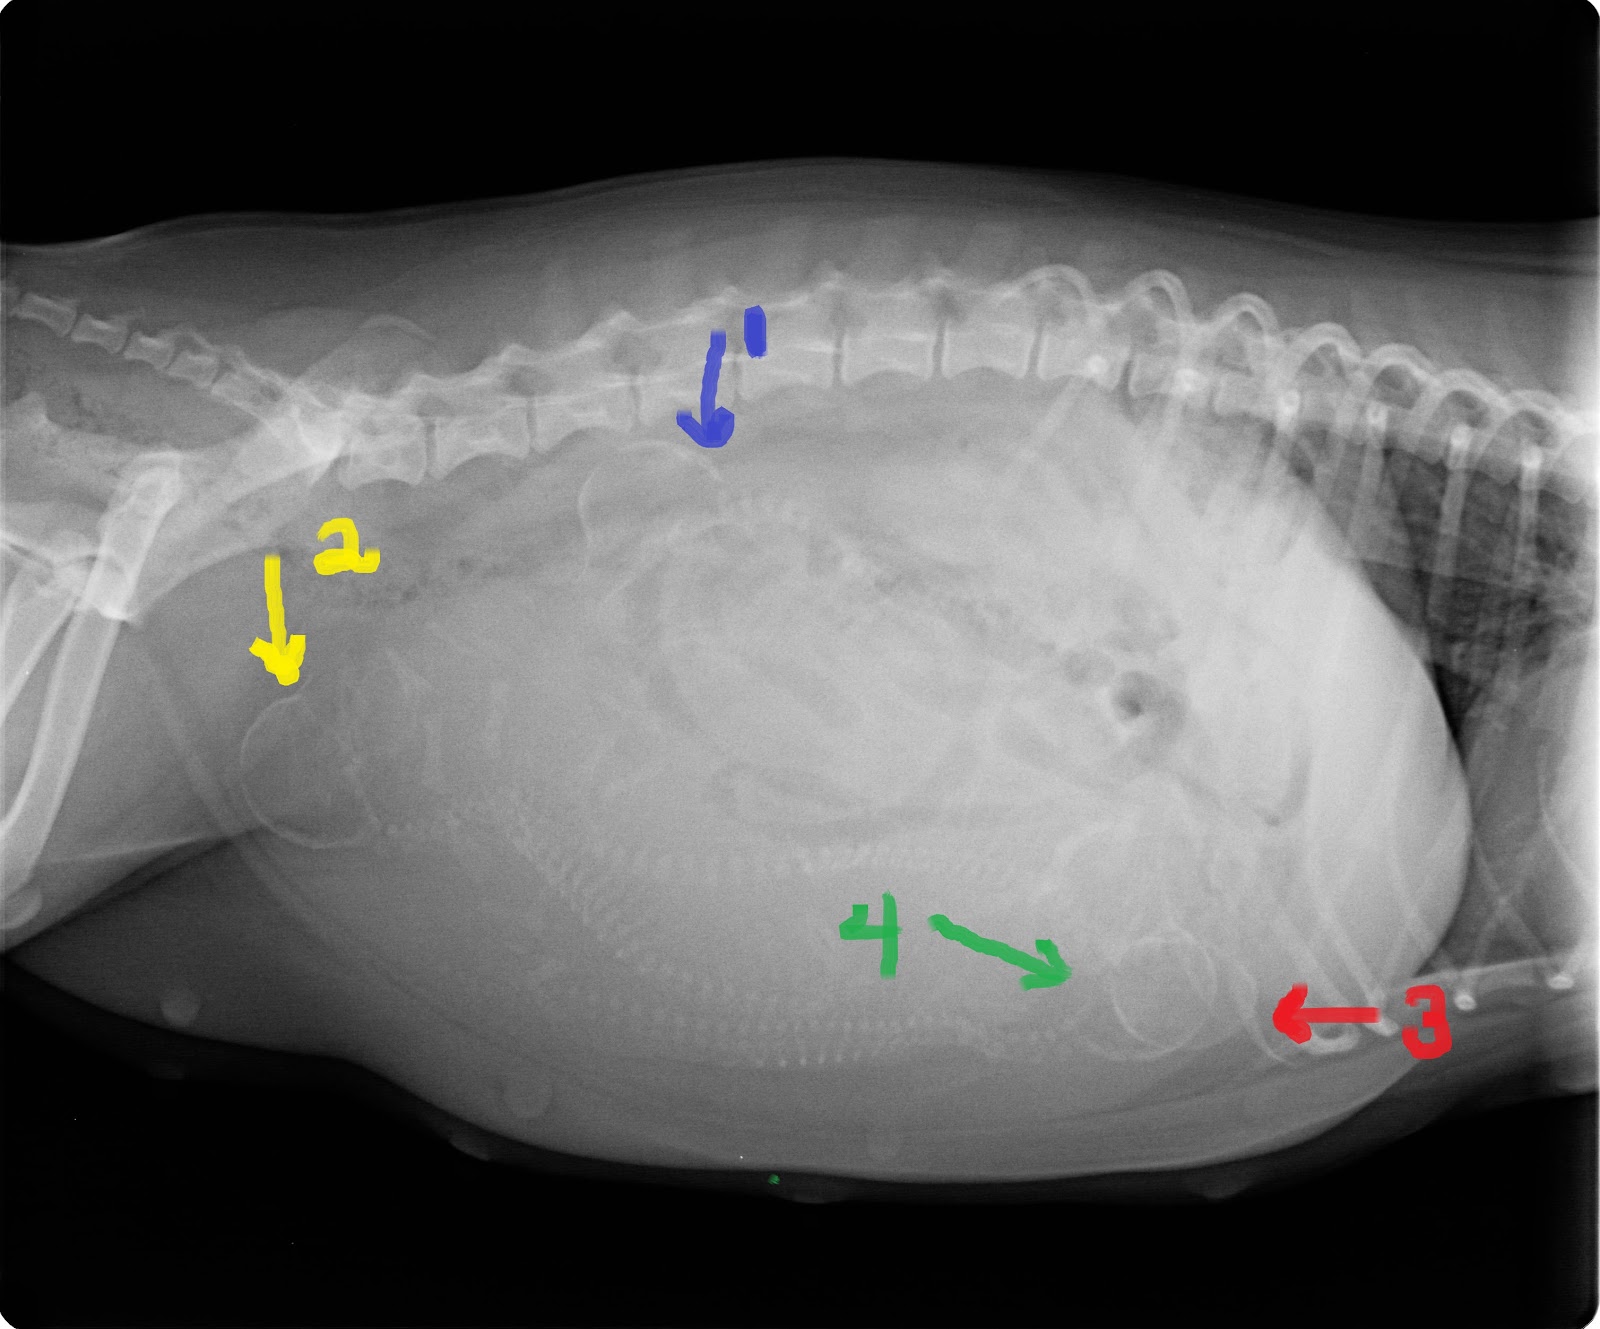

This last Tuesday, she went in for an xray so we could get a puppy count! :)

I was SO excited when the doc told me that 4 were on the way!

The more and more I looked at this xray when I got it home.. it seems like there are more than 4..

There were definetly more than 4 spines in there.. so we'll see! 4 was actually the most I expected for her first, but 5 or 6 wouldn't be too bad either.. :)I've been taking her temp a couple times a day.. So far, only 100 straight across. As soon 98 or 97 hits, I know it'll be go time!